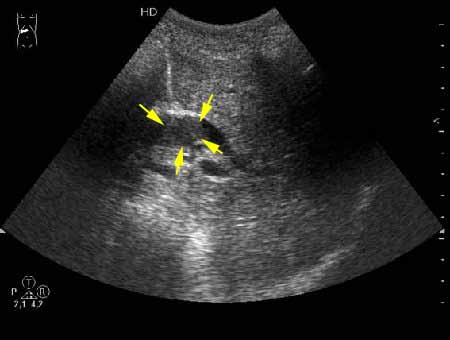

Дело в том, что в холедохе имеется нечто изоэхогенное (не знаю, видно ли это нечто на ваших мониторах). Врач УЗИ при осмотре перед поступлением в стационар на основании этой картины в заключении отметил возможность опухоли холедоха.

К сожаления, практически не видно. Если Вас не затруднит, пометьте стрелкой зону интереса.

А.М.Шифрин писал(а):К сожаления, практически не видно. Если Вас не затруднит, пометьте стрелкой зону интереса.

Гнойный холангит на фоне обструкции БДС конкрементом (камень вне скана). В холедохе определяется желчь с осадком, которая может быть ошибочно принята за его опухоль.